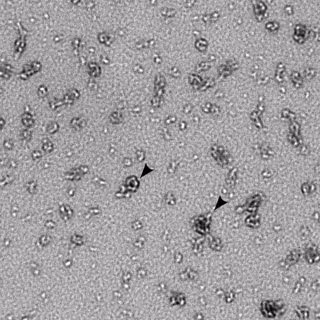

Algunos tipos de microbioma vaginal protegen contra la clamidia y otras ETS - FLICKR/NIAID - Archivo

Si bien se sospecha que la microbiota dominada por 'Lactobacillus' en la vagina de una mujer proporciona una barrera protectora contra las Enfermedades de Transmisión Sexual (ETS) como la clamidia, los investigadores quisieron explorar cuál era la comunicación entre el huésped de clamidia y el microbioma cervicovaginal para comprender mejor la resistencia y la susceptibilidad a esta infección.

Así, los científicos demostraron que los 'Lactobacillus iners', una bacteria que se encuentra comúnmente en la vagina, no protegía de manera óptima las células humanas contra la infección por clamidias, mientras que los productos de 'Lactobacillus crispatus', otra especie de 'Lactobacillus' que se encuentran con frecuencia en la vagina, sí.

Como ha explicado Patrik Bavoil, profesor en el Departamento de Patogénesis Microbiana de la Facultad de Odontología de la Universidad de Maryland, la clamidia tiene fama de ser el microorganismo más difícil de estudiar. Al esconderse dentro de las células, el patógeno evita rutinariamente las defensas antimicrobianas del huésped. Al causar una infección principalmente asintomática, a menudo escapa a la detección tanto del huésped infectado como del médico.